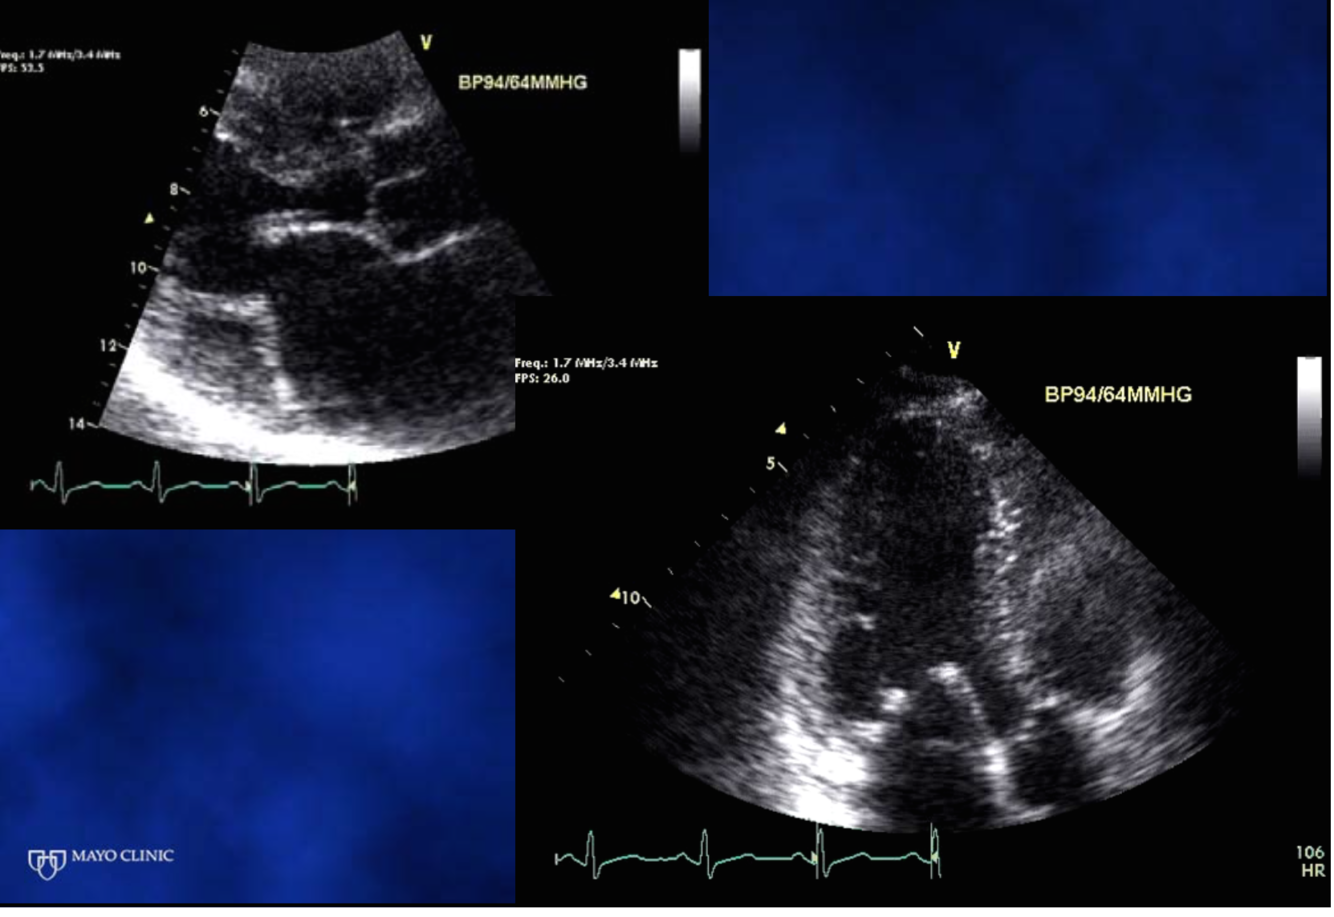

Diagnosis in each picture

PV systolic damping and Systolic flow reversal (from severe MR- goes UNDER the baseline)